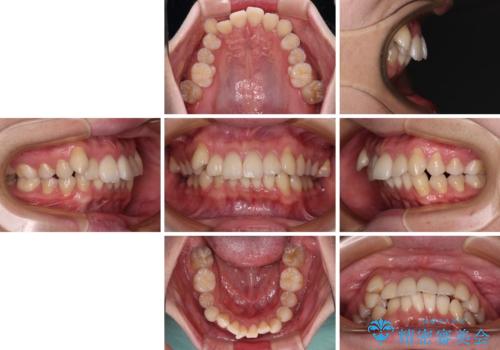

- 前歯のデコボコや八重歯を気にして来院された患者様です。

左右ともに奥歯の咬み合わせに問題があり、上顎臼歯が前方位にある状態で、結果として上顎前歯全体が前方位かつ叢生になっていました。

また、左右ともに上顎最後臼歯が頬側に転移していたため、補助装置を用いて舌側に移動をさせながら、上顎前歯を引っ込むように移動させることとしました。

口元の突出感を解消させるため上顎左右第一小臼歯2本を抜歯して、ワイヤー装置にて矯正治療を行うこととしました。